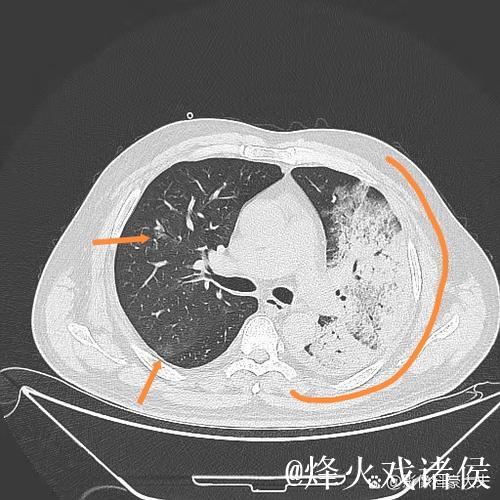

肺炎之所以让人恐惧,不仅因为它可能引发呼吸衰竭,甚至威胁生命,更因为它在短时间内剥夺了一个人对自己身体的信心。高烧、胸闷、呼吸困难,让人感到前所未有的无助。埃迪豪在住院期间,体验到那种“自己什么也做不了,只能依赖他人”的状态,这种深度依赖,让他对医护人员的信任不再停留在口头上,而是带着一种带有生死重量的感激。在无数次被抽血、做影像检查、调整药物方案的过程中,他感受到的是一种系统性的支撑机制从分诊、检查到治疗,再到随访,每一个环节都需要专业、协作和责任心。正是这种连贯的医护流程,让肺炎这样的急性疾病可以被及时识别和有效控制。

想象这样一个并不夸张的场景某个冬天的深夜,一位普通中年人因为持续高烧、咳嗽不止被家人紧急送往医院急诊。起初他以为只是普通感冒拖一拖就好,但胸闷和呼吸急促让他开始害怕。急诊医生为他安排了血常规、胸部影像检查,很快诊断出是肺炎并且已经出现肺部大片感染。值班的护士迅速为他建立静脉通路,挂上抗感染和补液的药物;呼吸科医生查看片子后,决定将他收入病房,密切监测血氧和生命体征。几天后,随着体温逐渐下降、咳嗽好转,他终于能平稳入睡。出院时,他握着主管医生的手说的一句“谢谢你们救了我”,背后是一整套完备的医疗体系在运转。这种经历,也正是很多人在重病之后才真正理解的现实只有当你真正被送进急诊室,才会明白一个反应迅速、配置合理、运行有序的医疗体系有多重要;只有当你在凌晨三点看到仍在查房的医生和整理病房的护士,才会明白医护人员的责任感远比外界想象更为沉重。